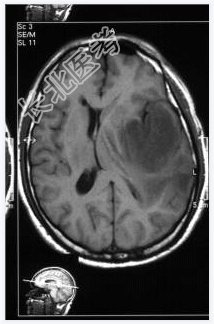

- [材料题] 患者,男性,58岁,因头疼1月余,伴嗜睡、记忆力下降、性格改变1周入院。头颅MRI检查。

- 简答题1、诊断及依据是什么?

- 简答题2、鉴别诊断有哪些?